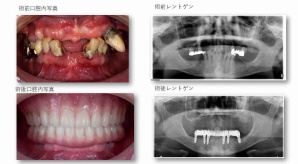

¥¤¥ó¥¹¥¿¥°¥é¥à¤ËºÜ¤»¤Æ¤¤¤ëÅö±¡¤Î¾ÉÎã¤Ç¤¹

ðÌî»õ²Ê¾ÉÎ㢠ÀèÅ··ç»¶ºÀµ¥¤¥ó¥×¥é¥ó¥È

ðÌî»õ²Ê¾ÉÎã¡¶ºÀµ¥¤¥ó¥×¥é¥ó¥È¥»¥é¥ß¥Ã¥¯